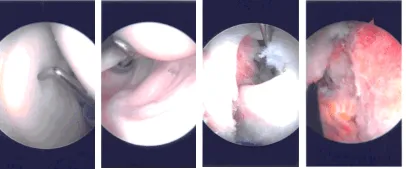

The anterosuperior entry portal was made with a spinal needle under arthroscopic supervision. Incision was given and examination of the cuff was space. with a spur. Probe was inserted from the anterosuperior portal. Glenoid as well as humerus as well as the scapula. The rotator Pictures were taken.

Trocar was inserted through the subscapularis and bursectomy was performed. Examination showed acromial roughening Examination of the rotator cuff showed high-grade partial-thickness tear in the anterior margin of the supraspinatus as well as in the rotator interval. The subscapularis was intact.

The decision was made to close the rotator cuff interval with the suture. The spinal needle was used to pass the PDS suture laterally and FirstPass was used to pass the suture medially. The arthroscope was entered into the glenohumeral joint to pass the suture superficial to the biceps tendon.

Once the suture was checked that it was not around the biceps tendon, the rotator cuff interval and the supraspinatus tear were closed with sliding knots. Acromioplasty was performed with the use of Coblation wand followed by burr.

Distal clavicle excision was also performed given the arthritis present. Coblation wand followed by burr was used to excise about a centimeter of the distal clavicle. The final pictures were taken and saved.

Intraoperative Arthroscopy Images